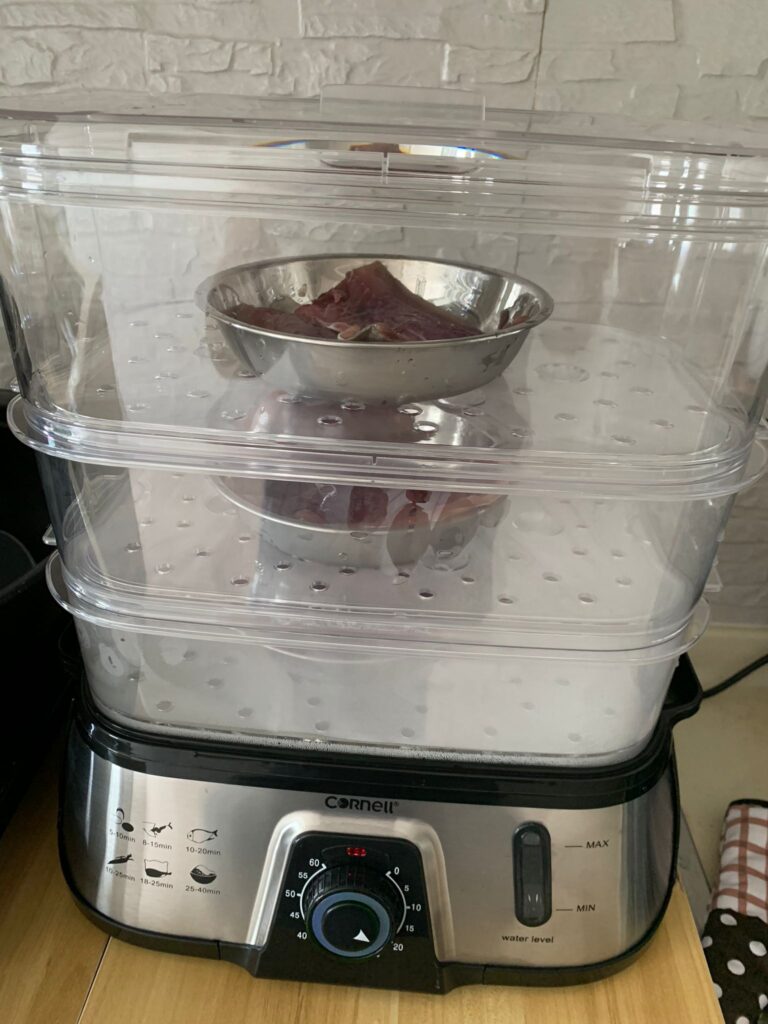

Morning: got helper in to cut nails, steam bath and clean ears. She can handle him alone. Given Subcut bupre n put on f patch for him.

Morning: got 2 helpers in to clean up and for him: cut nails, clean ears and steam brush fur. His f patch if off, given Subcut and bupre jab